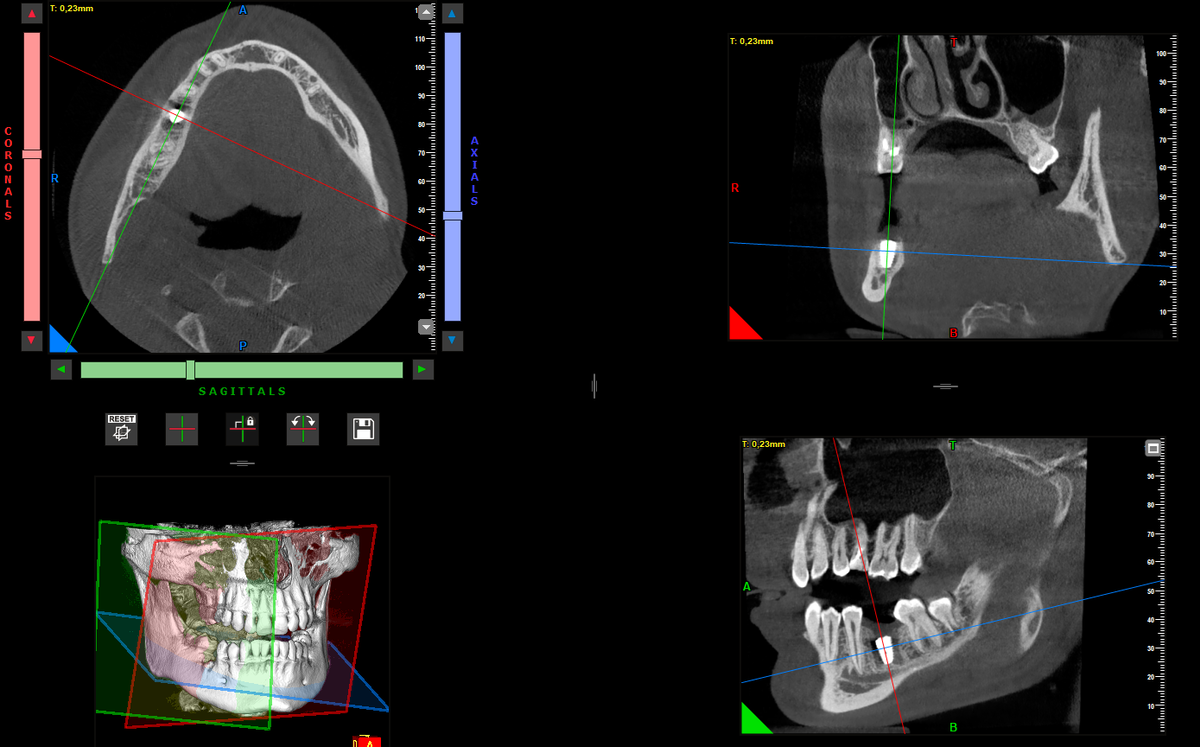

Контрольный снимок перед вторым этапом